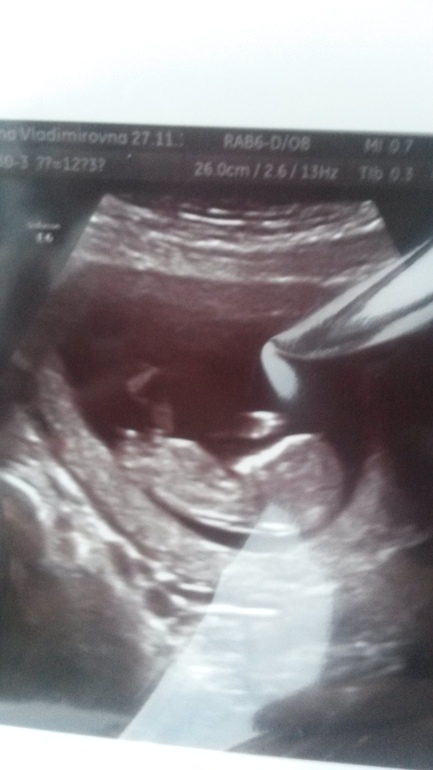

Первый скрининг пройден!

Поздравляю с хорошим скринингом! Очень хорошо видно, что мальчик) ножки раставил и перчик напоказ!!!!!